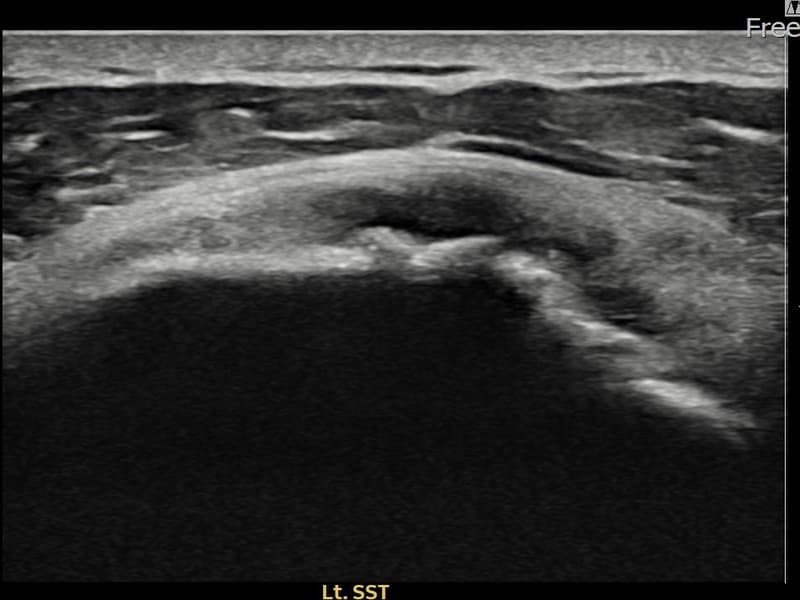

术前

术前超声确认左侧 冈上肌腱 광범위 部分撕裂,左侧冈上肌腱回声不连续伴肌腱缺损(15mm × 6mm (肌腱厚度约70%缺损))。术后超声显示撕裂部位充满再生组织,肌腱连续性恢复,回声模式正常化。

该患者持续肩痛。详细超声检查确认左侧 冈上肌腱 광범위 部分撕裂(缺损:15mm × 6mm (肌腱厚度约70%缺损))。在超声引导下实施非手术缩小缝合术。术后佩戴支具约4-6周,随后进行分阶段康复锻炼。随访超声确认肌腱连续性恢复、结构稳定,患者顺利回归日常生活。